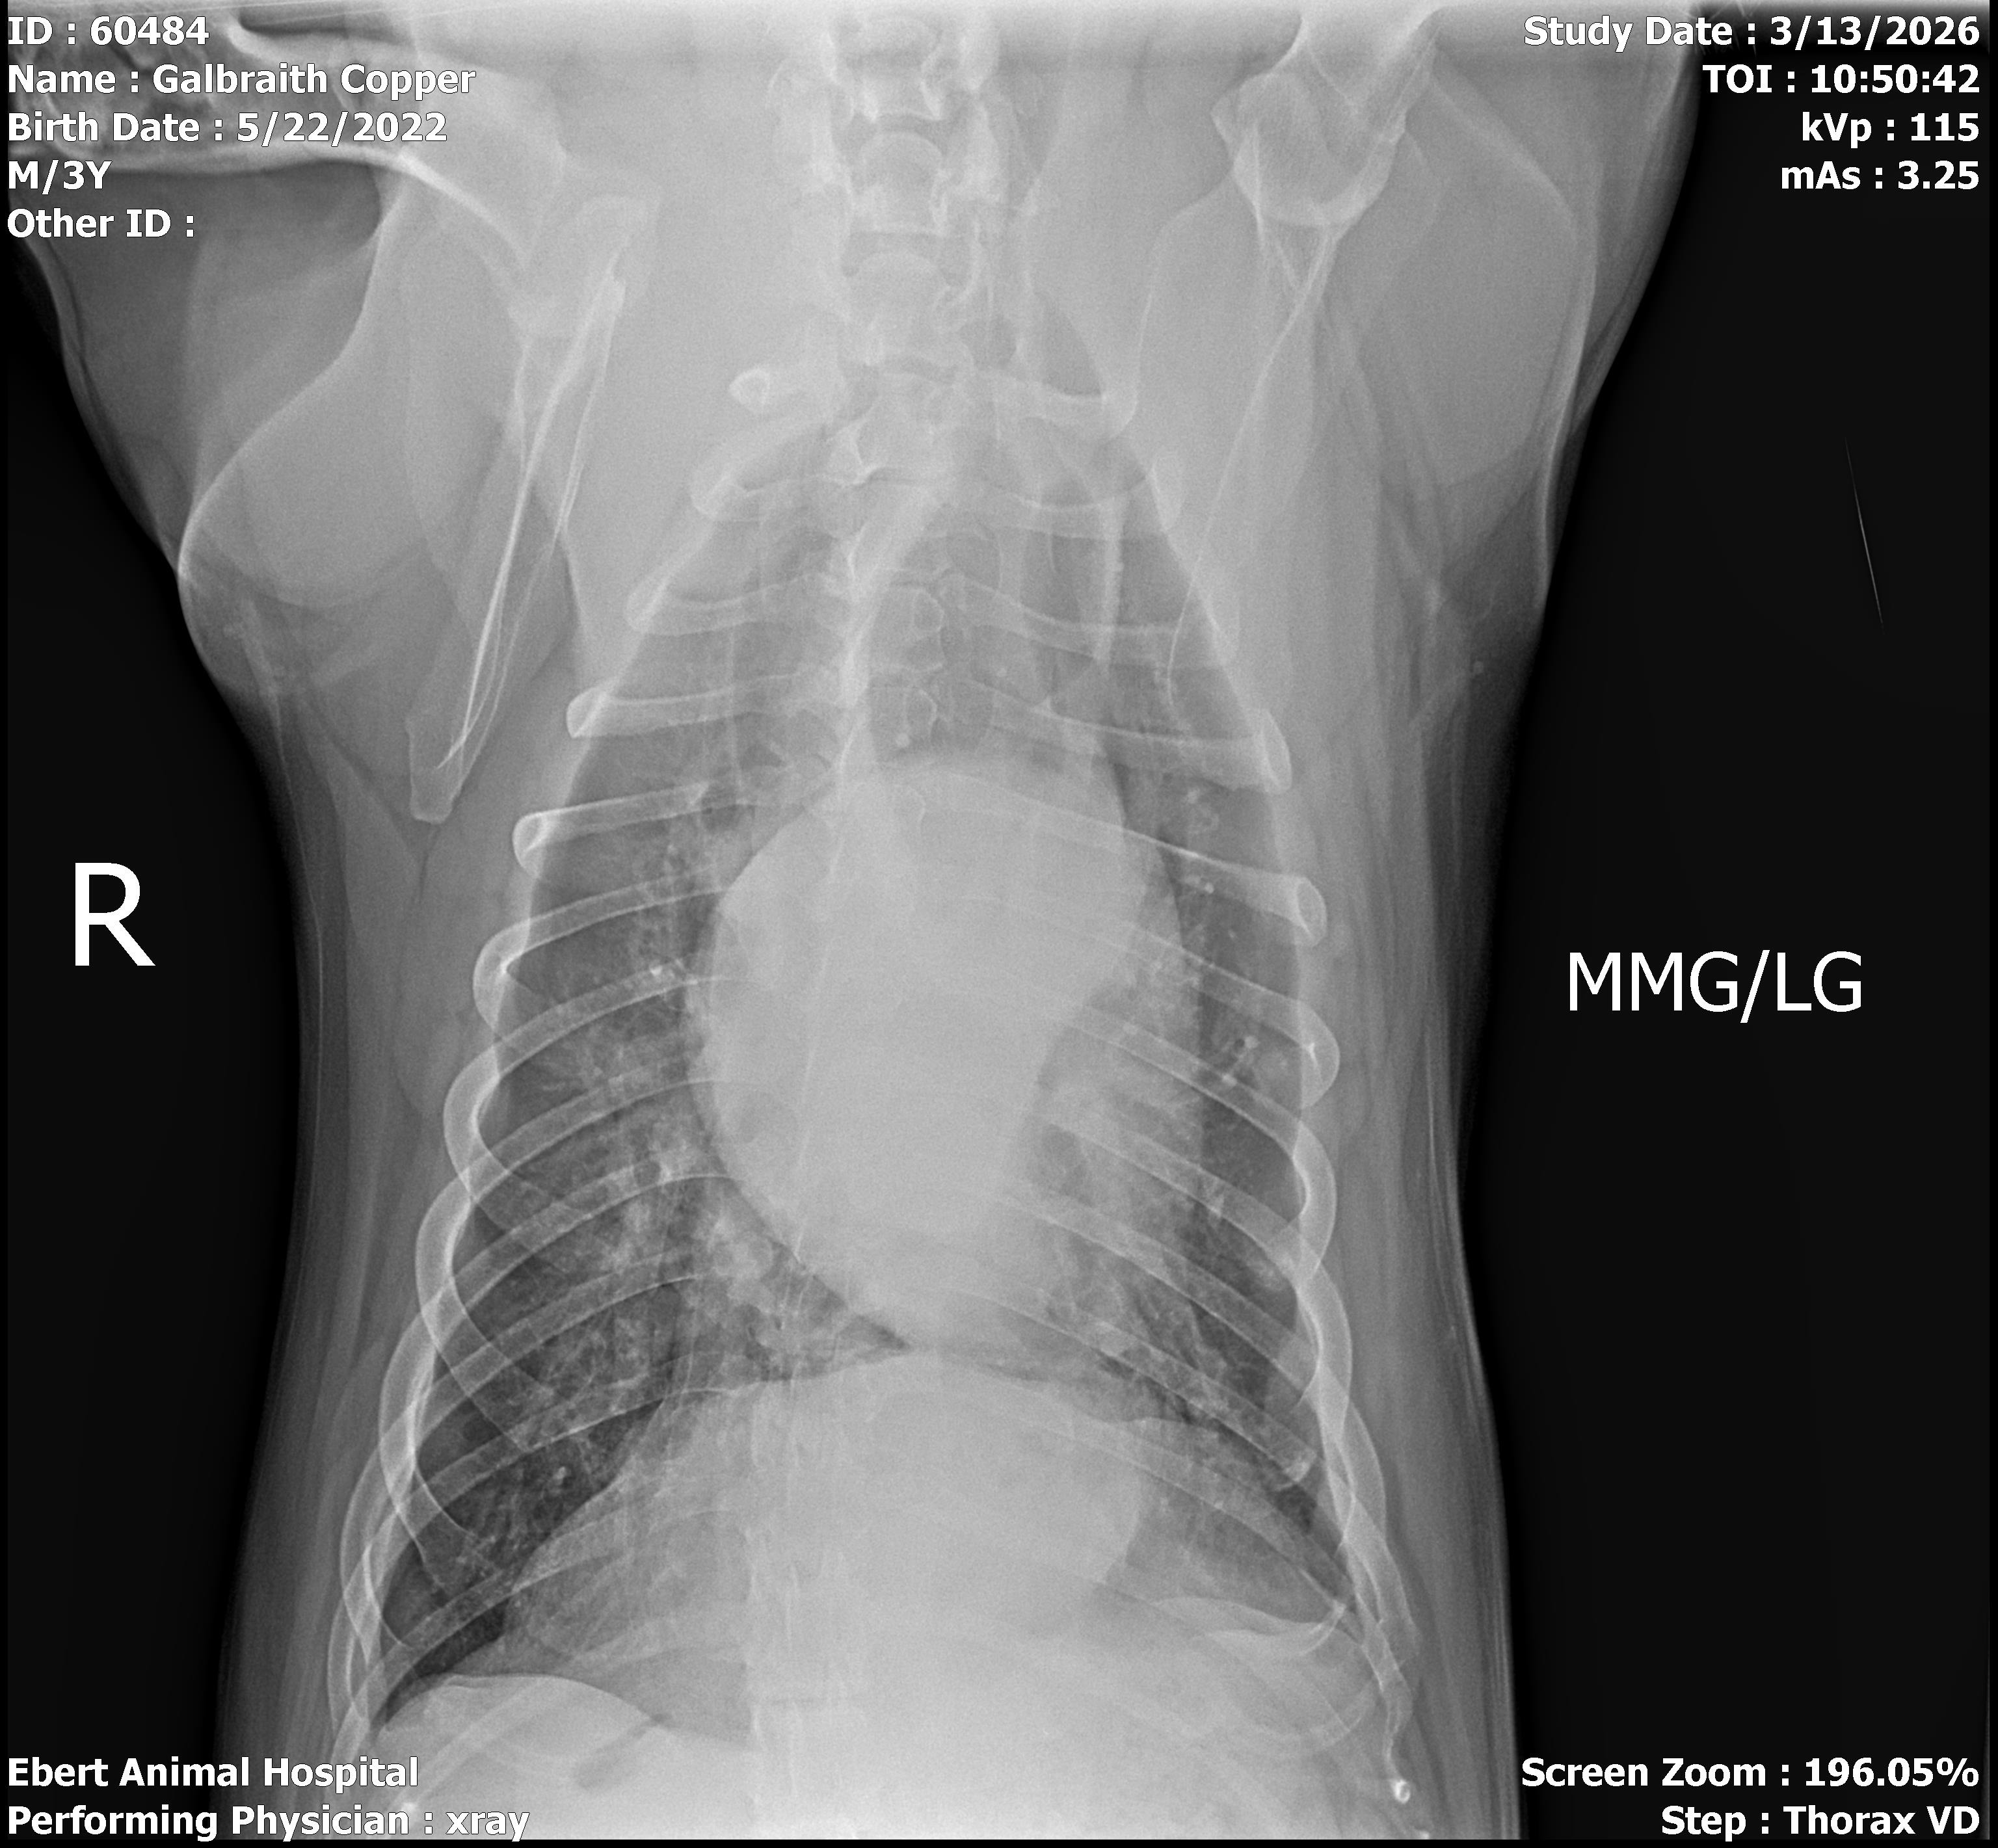

Hello, my name is June Galbraith. I am starting this for the second time because the first time didn't get enough $. This is to raise $ to cover the cost of my dog Copper's surgery. He has something stuck in his esophagus. Pet insurance doesn't pay till after we pay. So here we go. I hate doing this because I'm not one to ask for help, especially a second time. Yes, I had a GoFundMe but only raised $225.00. We need $4000. Copper is considered the neighborhood's dog. He stops to see anyone. We were very blessed to get him. Thank you for your generosity. God bless all of you for your help and prayers.